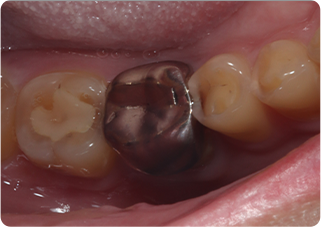

セラミックオーバーレイ症例①

術前

術中

術後

| 主訴 | むし歯の歯を治療をしたい |

|---|---|

| 治療期間/回数 | 3週間、3回 |

| 価格(税込) | 77,000円(税込) |

| リスク・副作用 | セラミックの破損、一時的な知覚過敏が生じる場合がある |

| ポイント | ラバーダム防湿下で接着することにより、歯とセラミックが一体化することを狙った。オーバーレイにすることで、歯ぐきに近い健康な歯質を削らずに治療することができる。 |